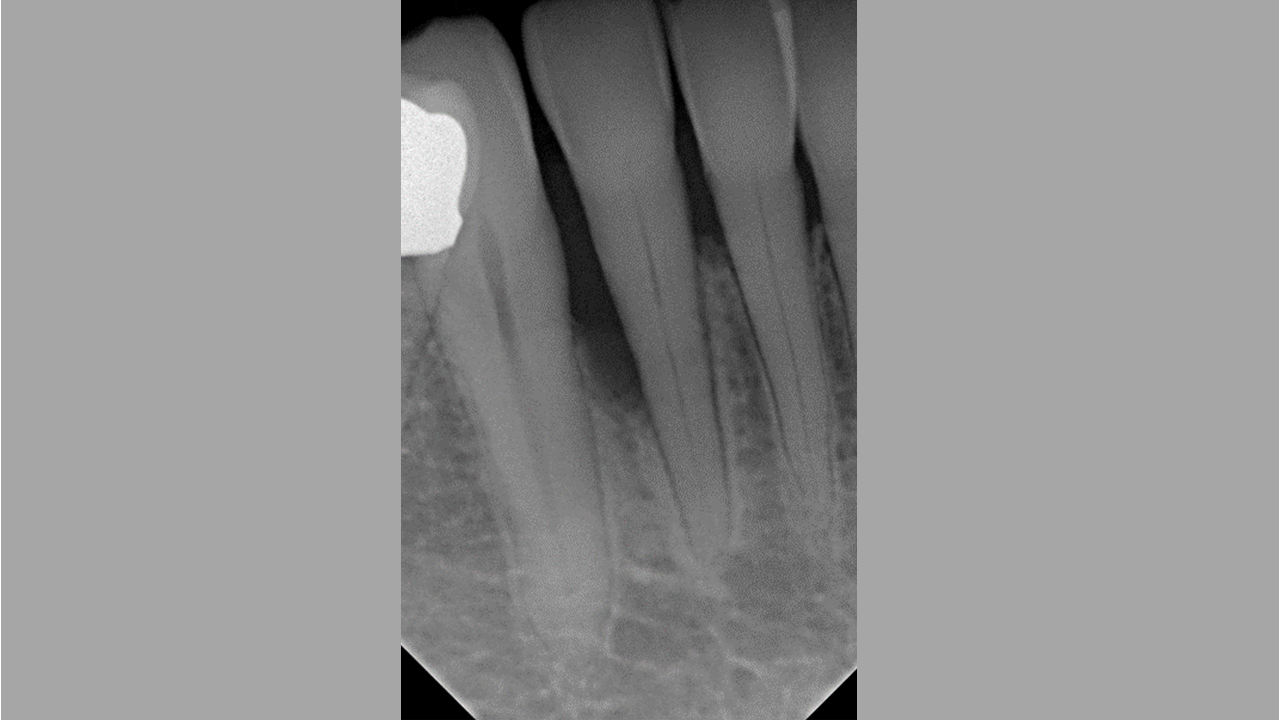

03/08 - Radiograph showing a deep intrabony defect on the distal aspect of tooth 42.

Non-contained intrabony defect treated using Straumann® Emdogain® and a synthetic bone grafting material - Prof. Dr. Dr. A. Kasaj